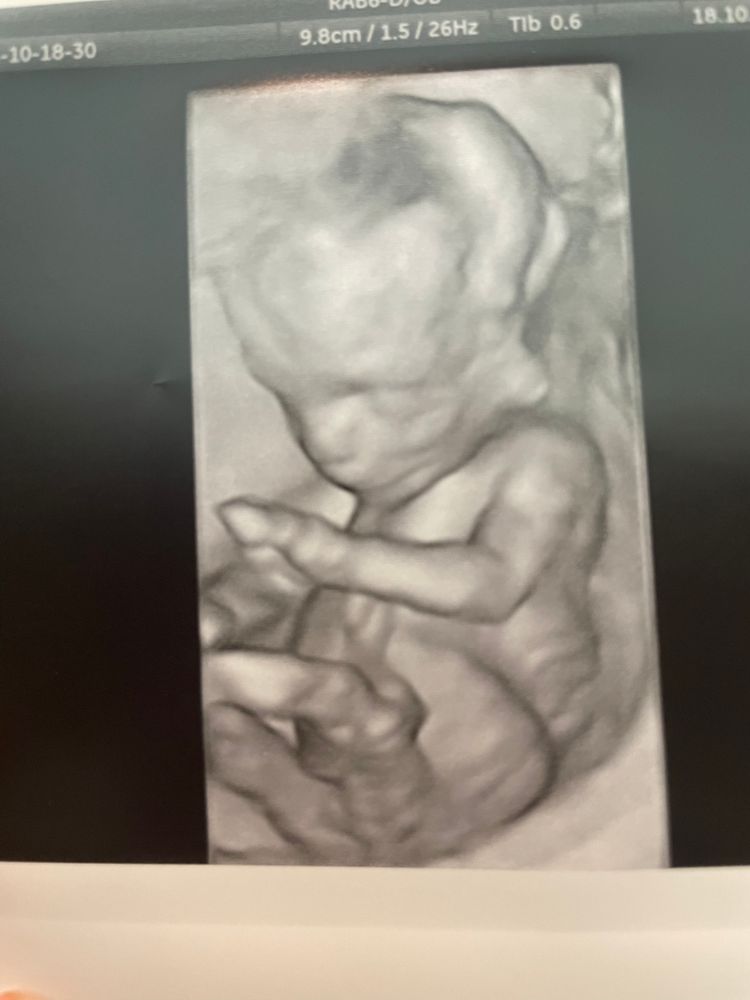

Как думаете мальчик или девочка ? 14 недель Все фото какие есть )

ничего не видно, а раз ничего не видно, то девочка скорее всего)

Надо фото в 2D лучше и снизу, со стороны попы.

На верхнем на девочку похоже, на нижнем не понятно, немного размазано 🤷‍♀️

Nastia Lu, на последнем на мальчика похоже.

Олюшка78, добавила ещё одно фото в коменты, сказала врач, что явного пениса не видно но в 12 недель сказали больше на мальчика похоже 😅